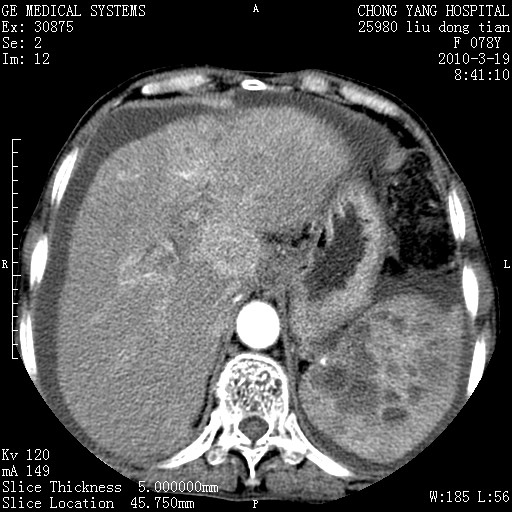

标题: CT25199:F 78Y 腹胀半年 消瘦乏力 [打印本页]

胆囊壁增厚并明显强化,胆囊癌伴多发转移瘤可能性大,淋巴瘤不除外,右肾囊肿,胸腹水.

考虑nhl,肝、脾、腹膜腔及腹膜后多发淋巴结受侵,腹水,右肾囊肿,慢性胆囊炎,右侧少量胸腔积液。

胆囊有软组织影有强化,支持胆囊癌,肝脾、腹膜后淋巴结转移。

nhl的淋巴结多围绕主动脉,而且主动脉会移位,所以不考虑nhl。

分开来讲:肝左叶、尾叶病灶有不均强化像肝癌;

脾脏病灶无强化,像多发囊肿或淋巴管瘤,不除外淋巴瘤(低强化);

胆囊增生性病变:胆囊癌,腺肌增生症,慢性胆囊炎;

肝门、胰腺头、腹膜后多个团块: 淋巴瘤,转移;

腔静脉肝内段细小有无布加可能?

一元论最好了 淋巴瘤所致改变; 胆囊癌转移不像,胆囊周围肝组织清晰,肝癌淋巴结转移?三元论都不止。

最后报的胰头癌多发转移,脾脏单独考虑囊肿或淋巴管瘤。